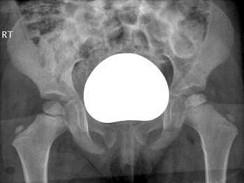

问题 女,4岁,左腿跛行2个月。结合图像,最可能的诊断是?(?)

选项 A.骨囊肿 B.软骨肉瘤 C.骨肉瘤 D.髋关节结核 E.股骨头骨骺缺血坏死

答案 E